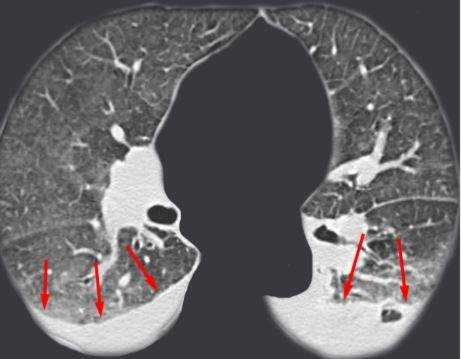

Выпот (красные стрелки) в обеих плевральных полостях.